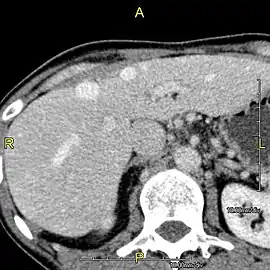

- Axial CT image showing anomalous hepatic veins coursing on the liver's subcapsular anterior surface[70]

- Maximum intensity projection (MIP) CT image as viewed anteriorly showing the anomalous hepatic veins coursing on the anterior surface of the liver

- Lateral MIP view in the same patient as previous image

- A CT scan in which the liver and portal vein are shown